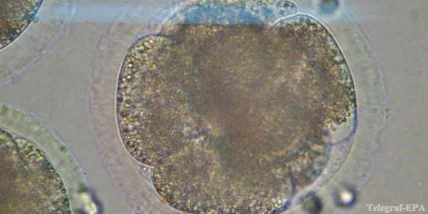

Полученный эмбрион успешно развивался 5-6 дней и достиг размера в 120 клеток, после чего Миталипову удалось извлечь из него живые стволовые клетки. Именно с них начинается развитие любого многоклеточного организма, они могут превращаться в клетки различных органов и тканей, что открывает широкие перспективы для лечения болезней, в том числе рассеянного склероза и болезни Альцгеймера.